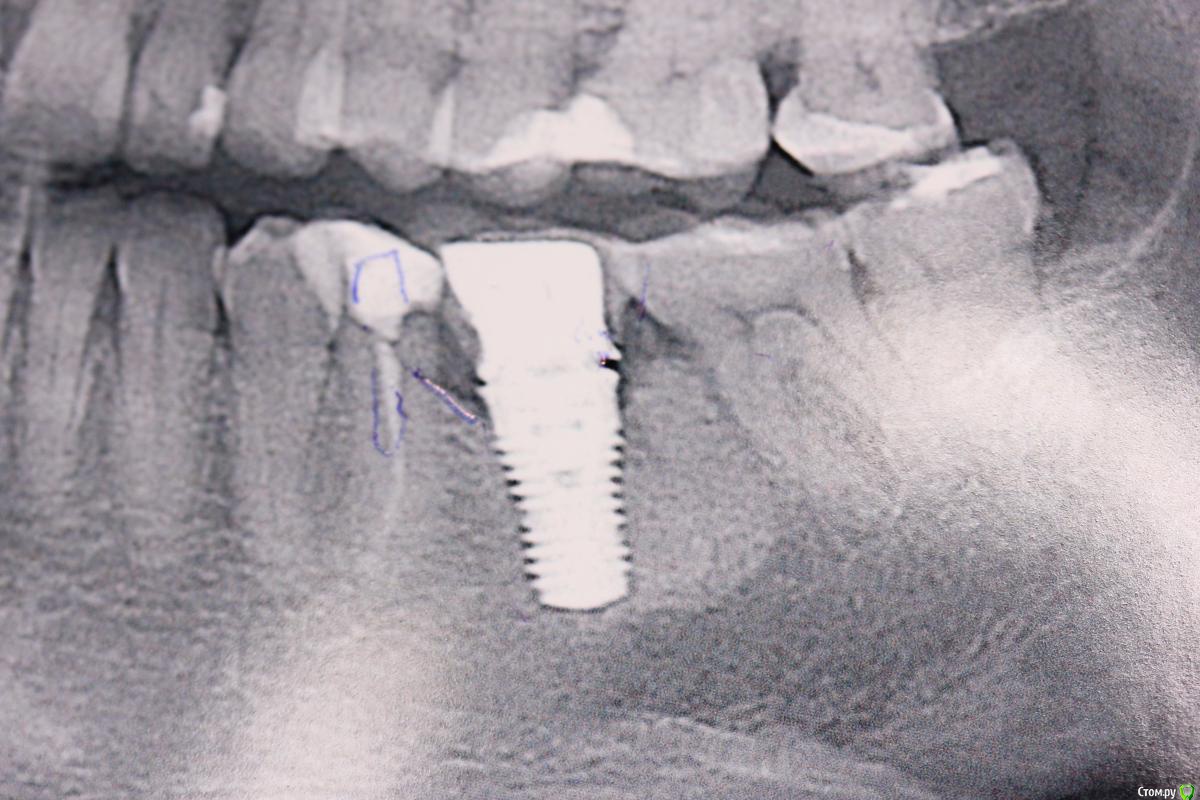

Доктор Добрых Дел Опубликовано 21 марта, 2016 Поделиться Опубликовано 21 марта, 2016 Похоже на straumann TE. Но на 100% не уверен. 2 Ссылка на комментарий

andr99 Опубликовано 21 марта, 2016 Поделиться Опубликовано 21 марта, 2016 Straumann TE. Судя по всему, WN (широкая шейка) 1 Ссылка на комментарий

Kazaev77 Опубликовано 23 марта, 2016 Автор Поделиться Опубликовано 23 марта, 2016 Спасибо. Точно она. Нашел и аналог 1 Ссылка на комментарий